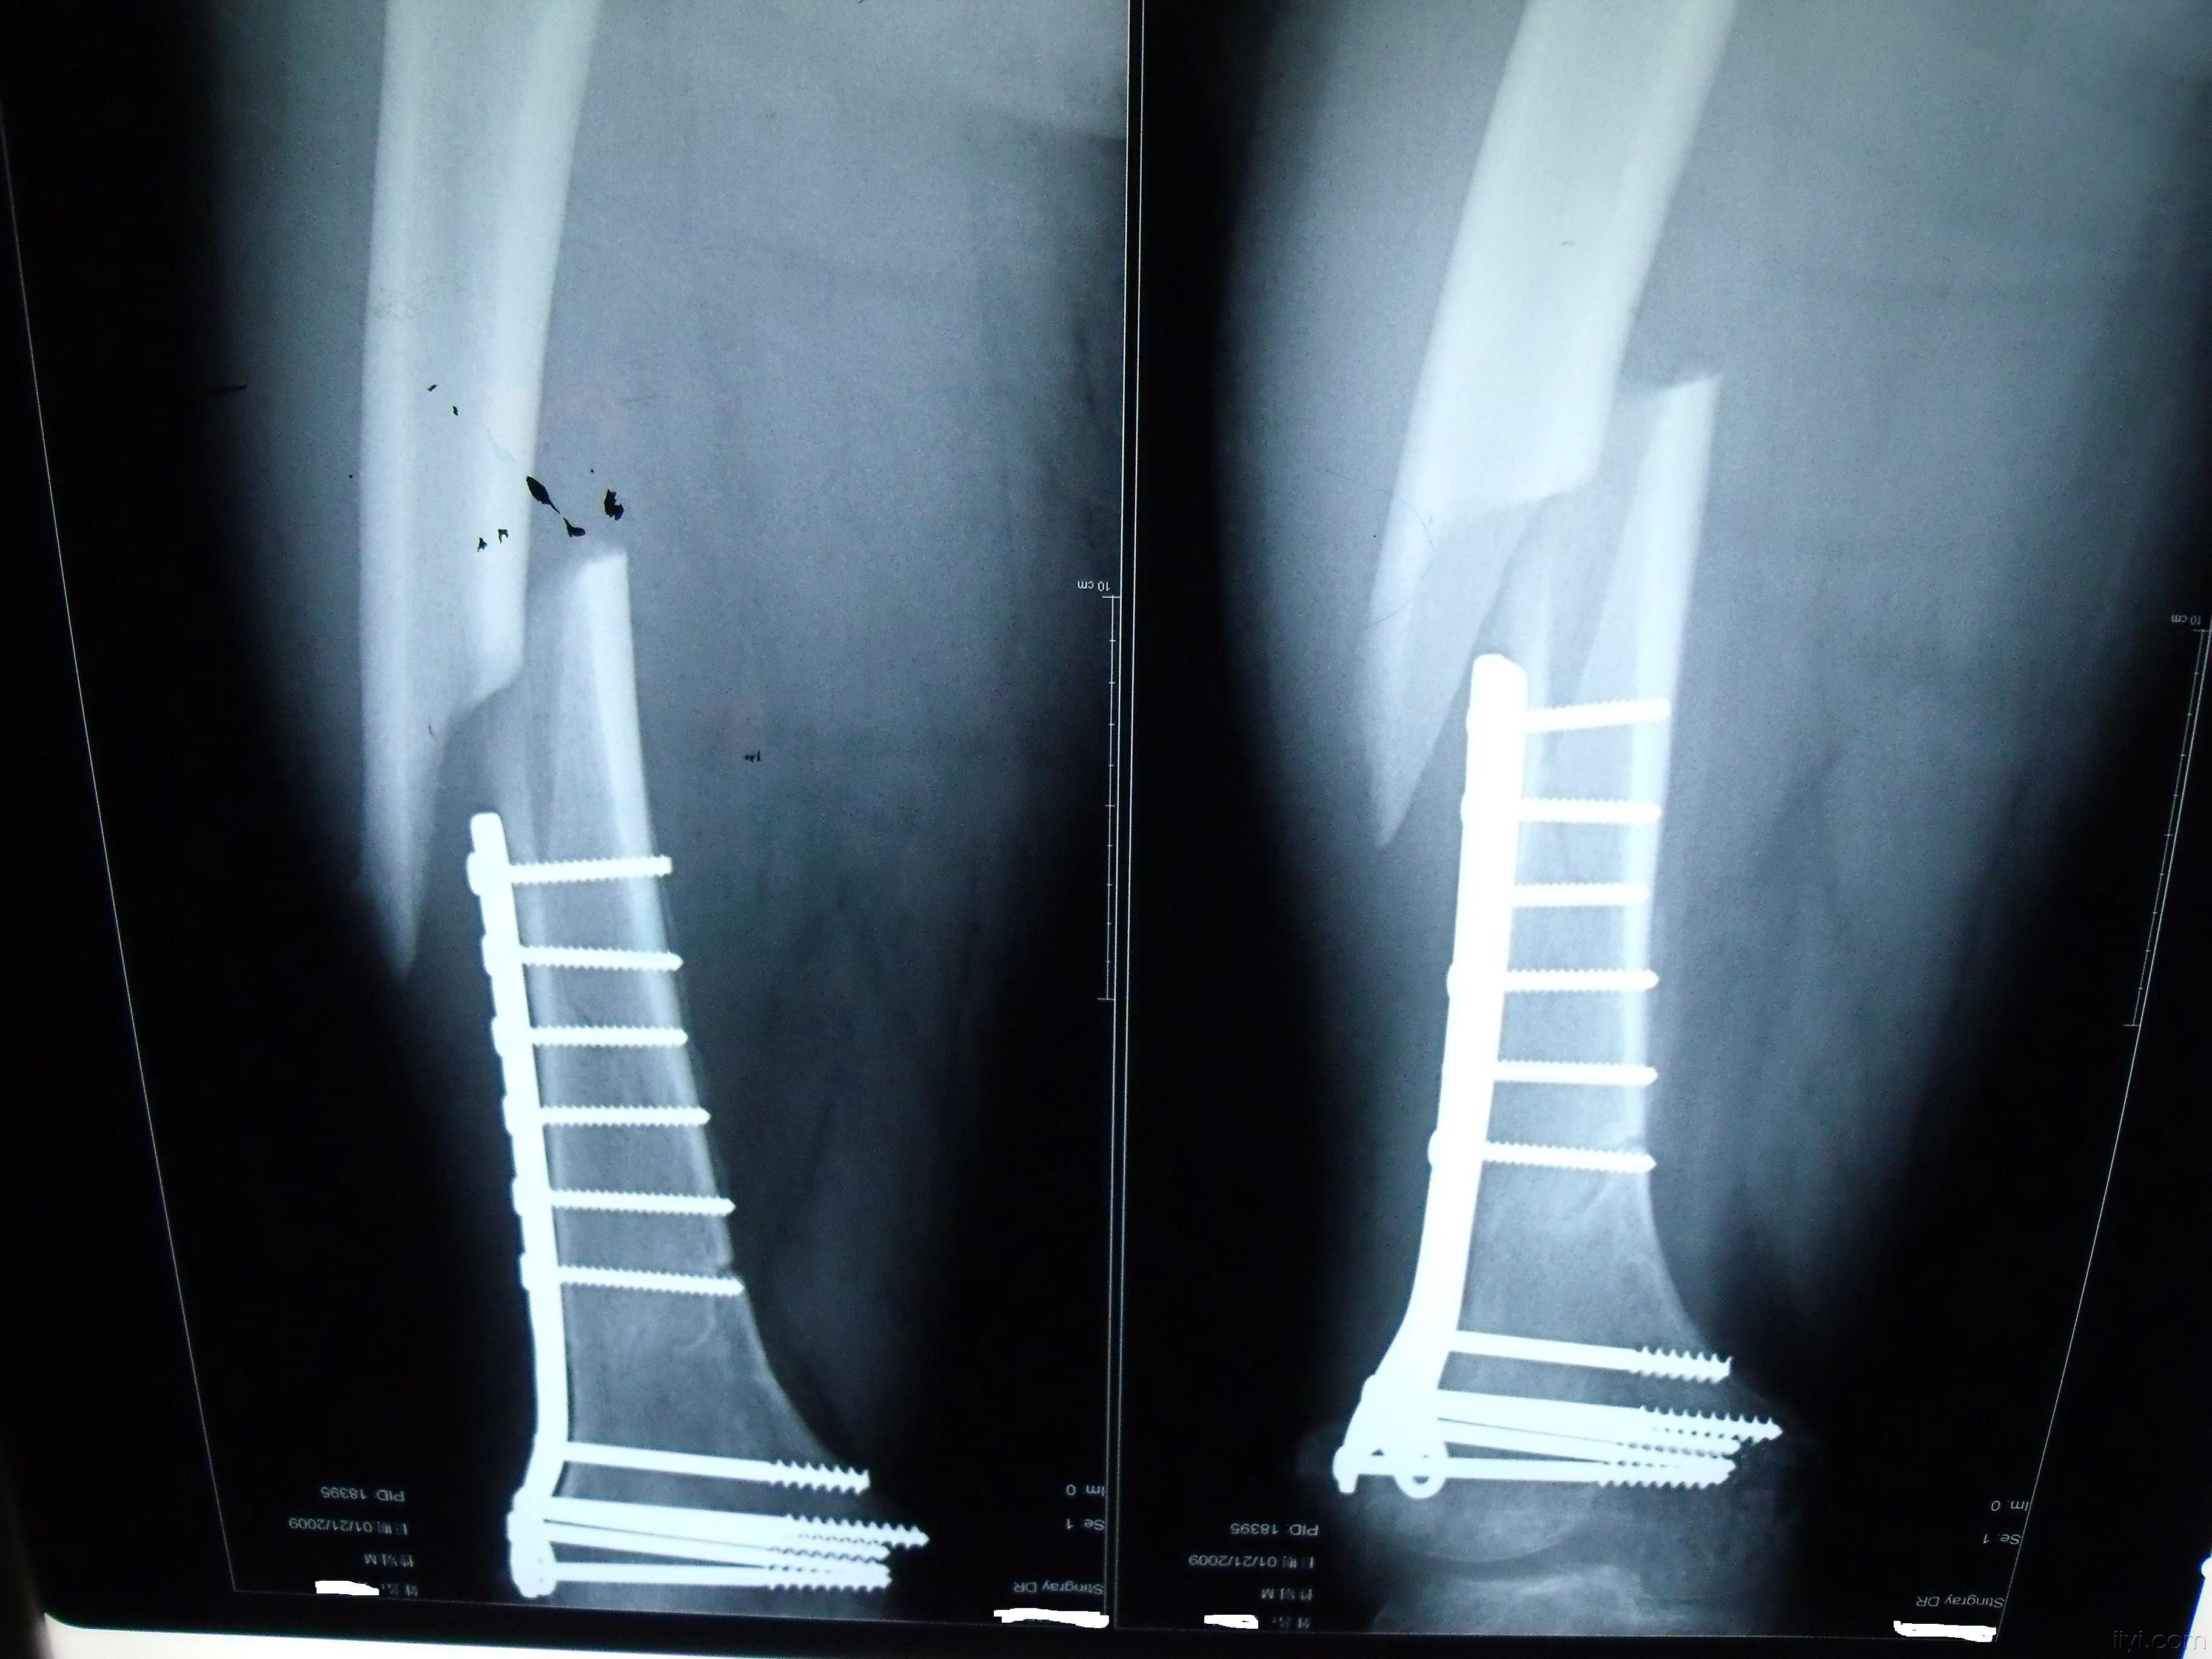

49岁股骨远端骨折微创复位锁定钢板内固定手术一例